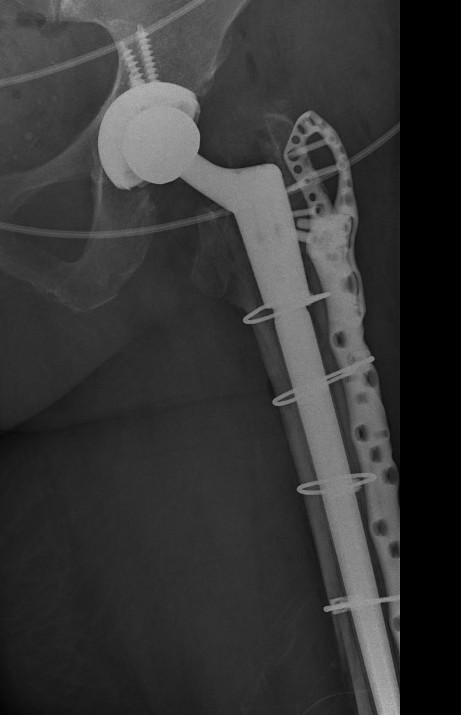

Revision uncemented arthroplasty with Zimmer cable plate

Long stem uncemented revision with cortical strut allograft

Long stem uncemented revision with plate + cortical struts